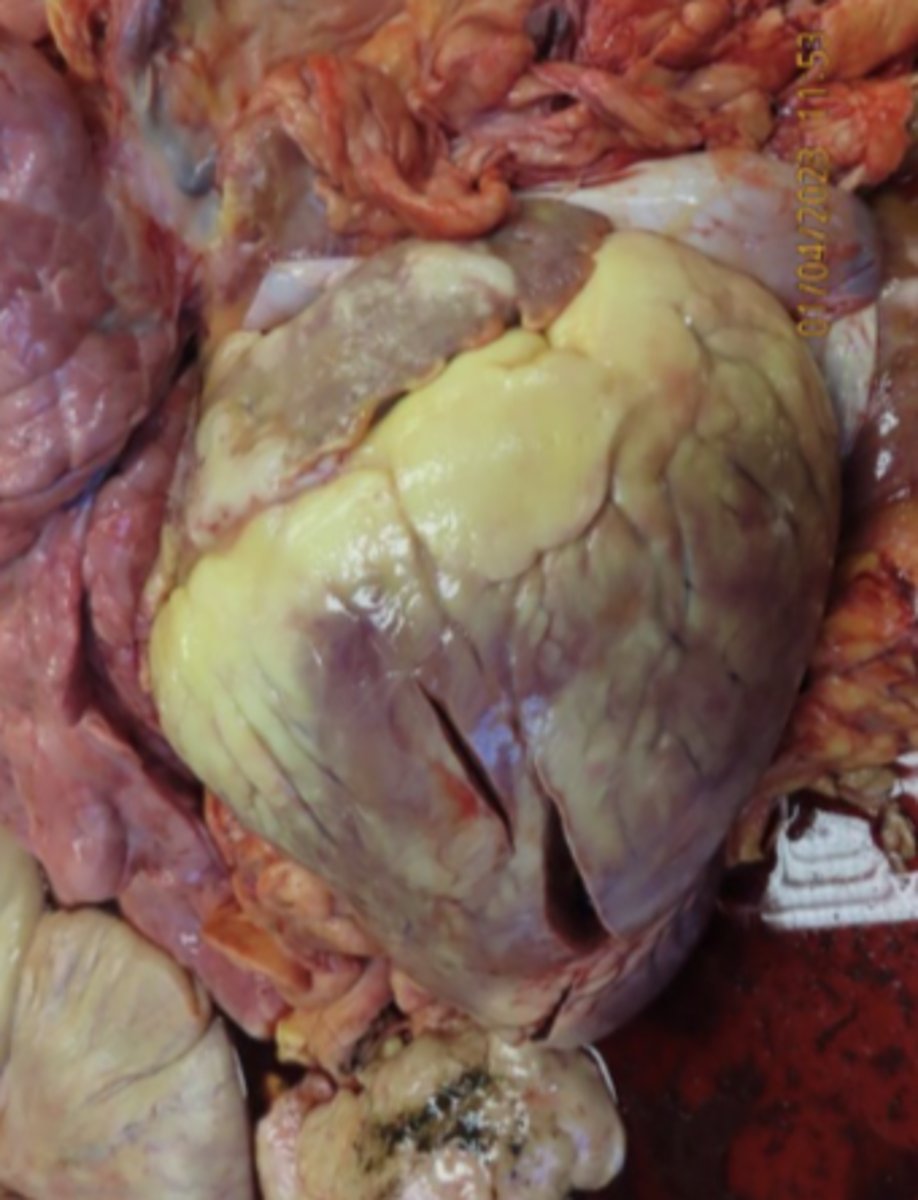

BLV

What has caused the gross appearance of this bovine heart?